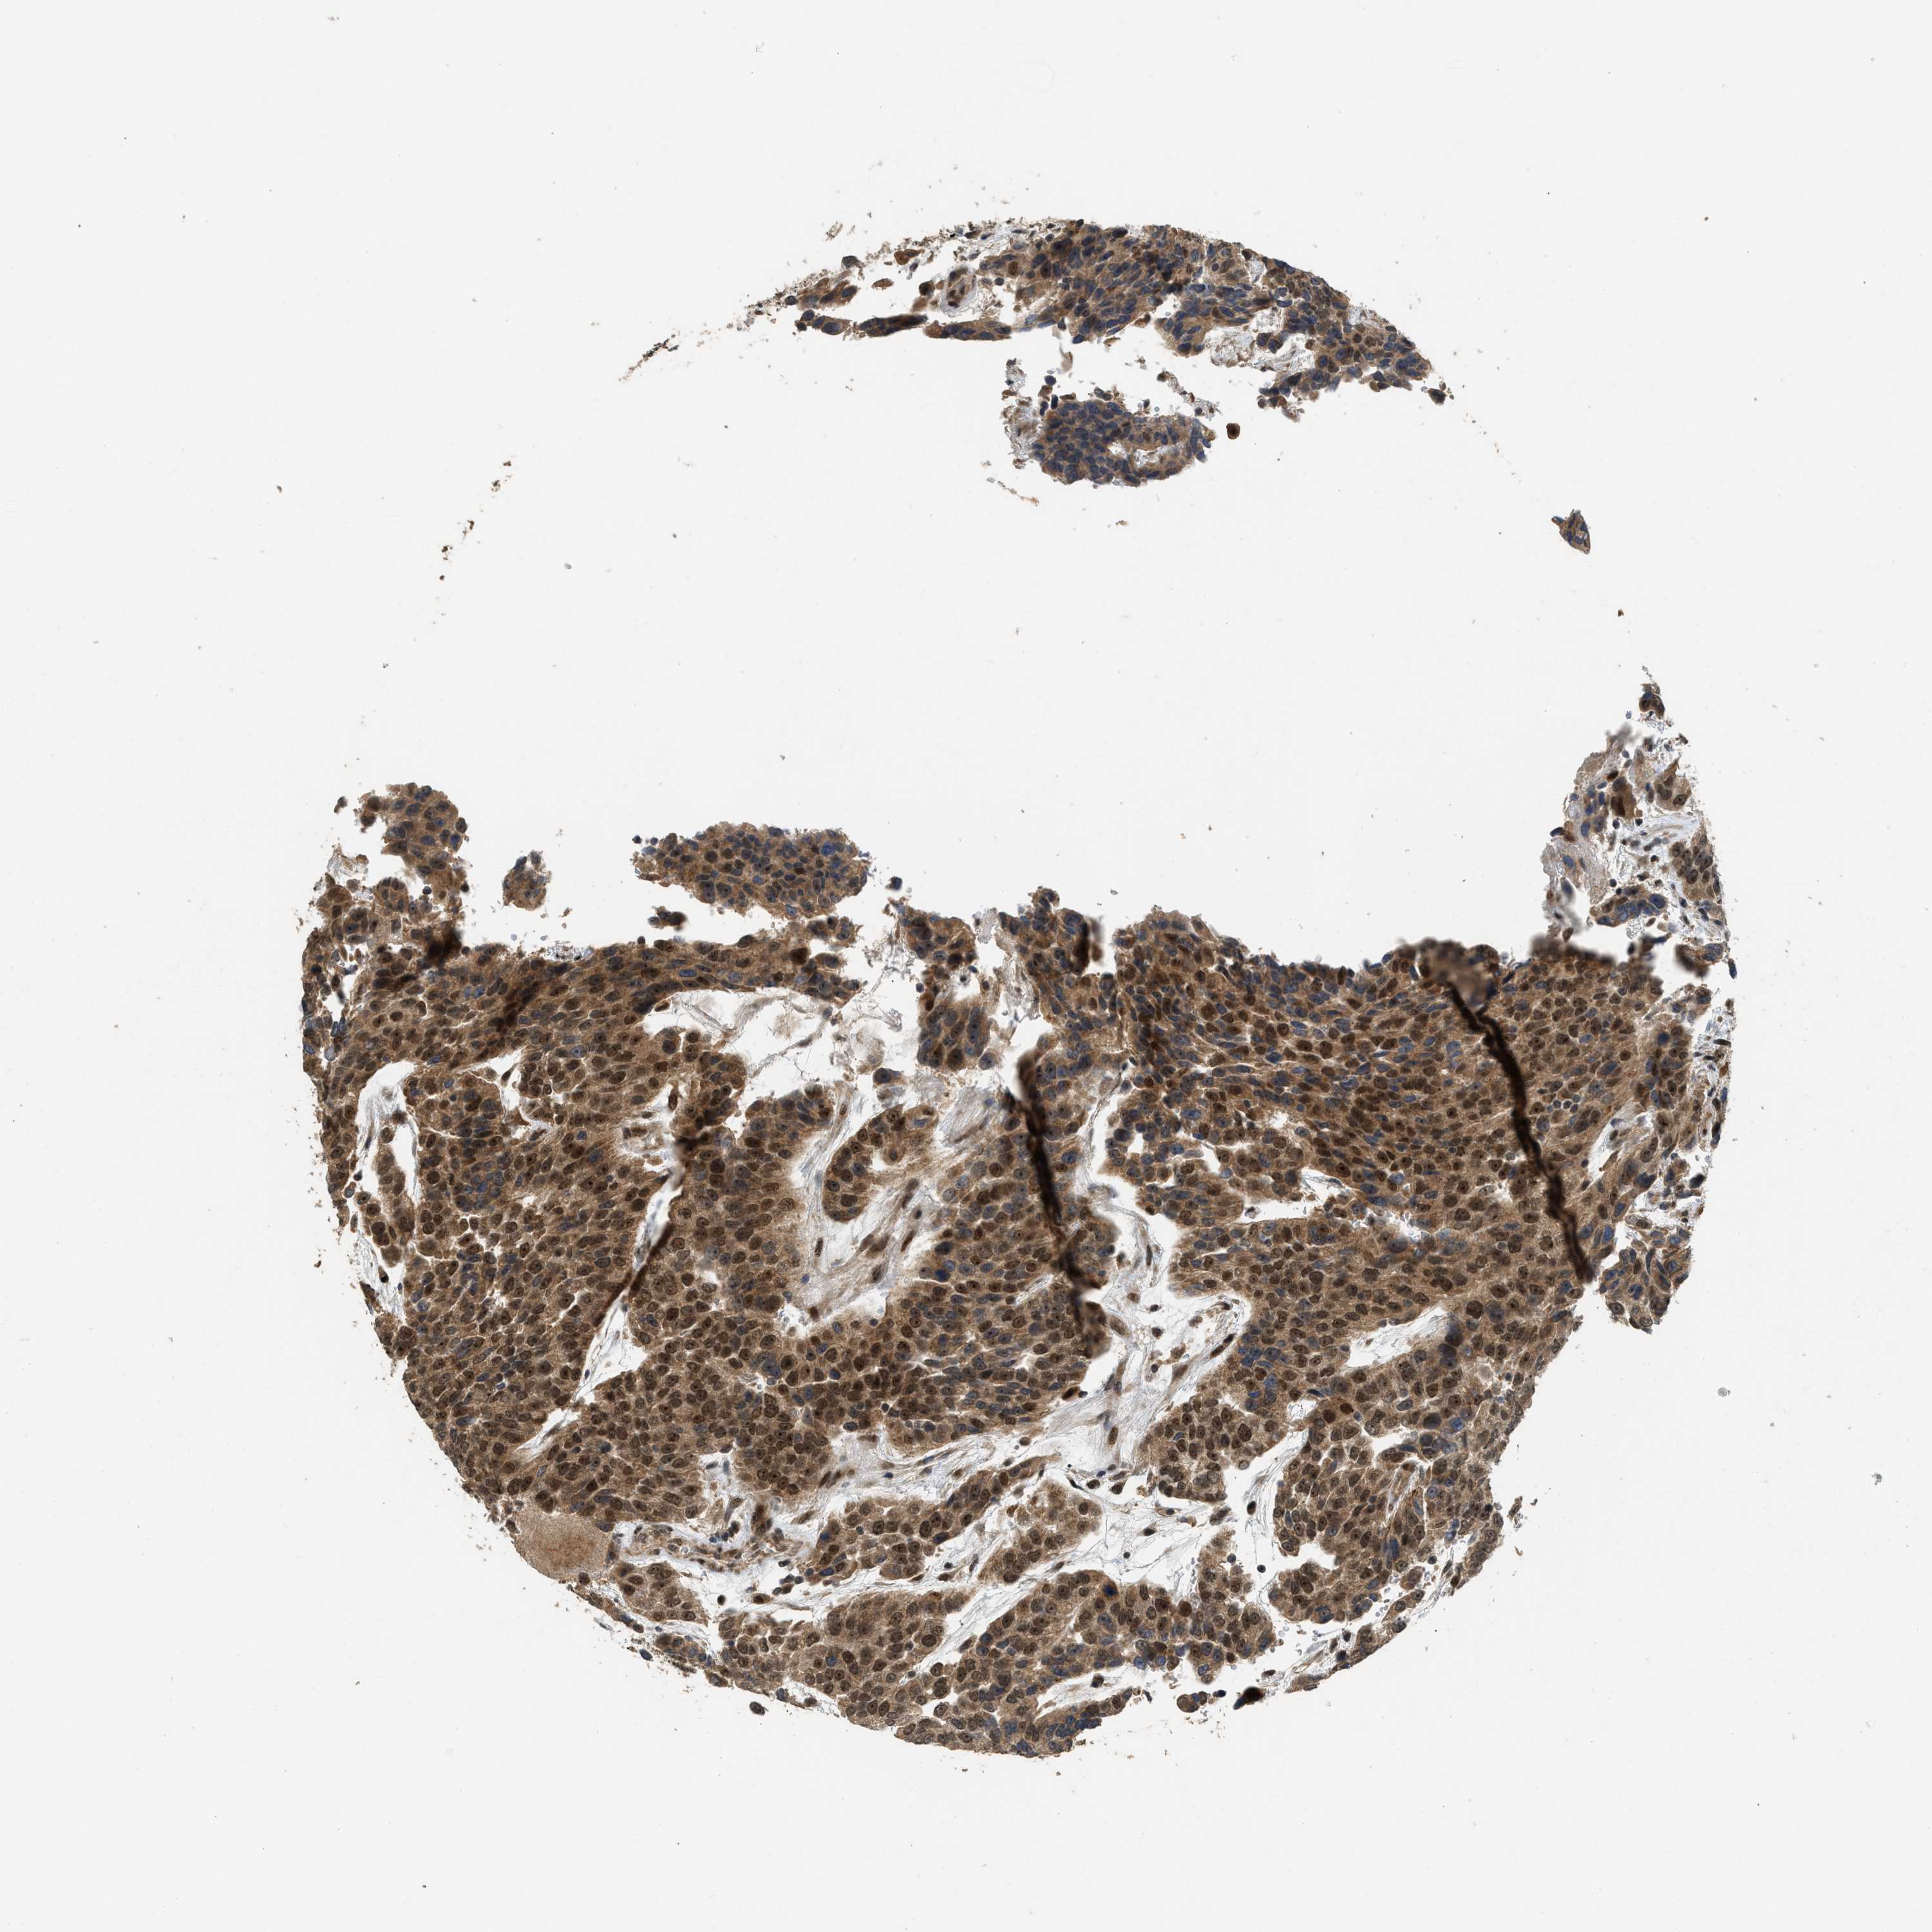

UROTHELIAL CANCER - Protein expressioni

A mouse-over function shows sample information and annotation data. Click on an image to view it in a full screen mode. Samples can be filtered based on level of antibody staining by selecting one or several of the following categories: high, medium, low and not detected. The assay and annotation is described here.

Note that samples used for immunohistochemistry by the Human Protein Atlas do not correspond to samples in the TCGA dataset.

Antibody stainingi

Antibody staining in the annotated cell types in the current human tissue is reported as not detected, low, medium, or high, based on conventional immunohistochemistry profiling in selected tissues. This score is based on the combination of the staining intensity and fraction of stained cells.

Each image is clickable and will lead to virtual microscopy that enables deeper exploration of all samples and also displays staining intensity scores, fraction scores and subcellular localization as well as patient and tissue information for each sample.

Antibody HPA018527

Staining

High

Medium

Low

Not detected

Intensity

Strong

Moderate

Weak

Negative

Quantity

>75%

75%-25%

<25%

None

Location

Nuclear

Cytoplasmic/membranous

Cytoplasmic/membranous,nuclear

Urothelial carcinoma, Low grade

Urothelial carcinoma, High grade